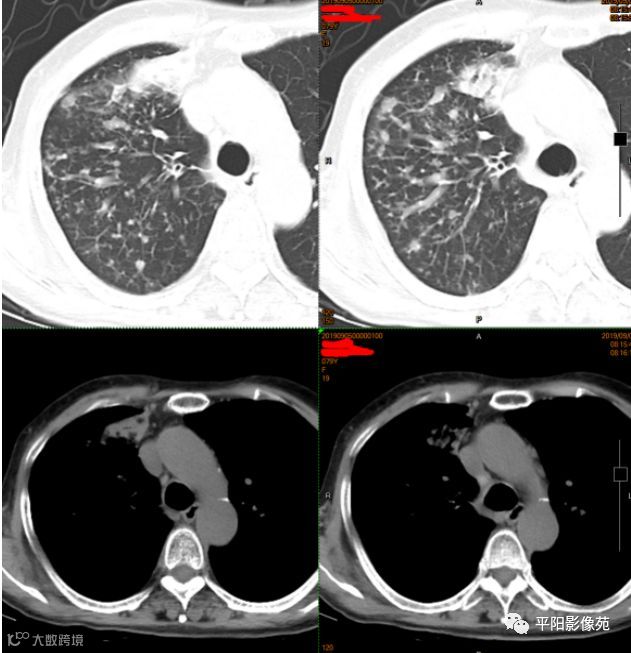

影像检查

右主支气管壁及分支壁肥厚,伴右肺上叶弥漫小叶间隔结节样增厚,不除外中央型肺癌伴癌性淋巴管炎可能。

本例影像特点,右主支气管壁肥厚,管腔狭窄不明显,管壁内缘光滑,管腔内有明显病灶堵塞,且远侧各段支气管与其他肺叶表现相同,肺内多发树叶征及实变影。